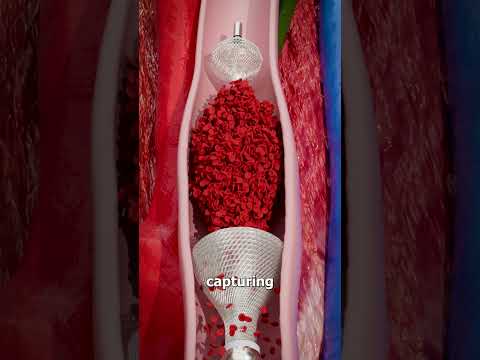

Removing Blood Clots with Vacuum 😨